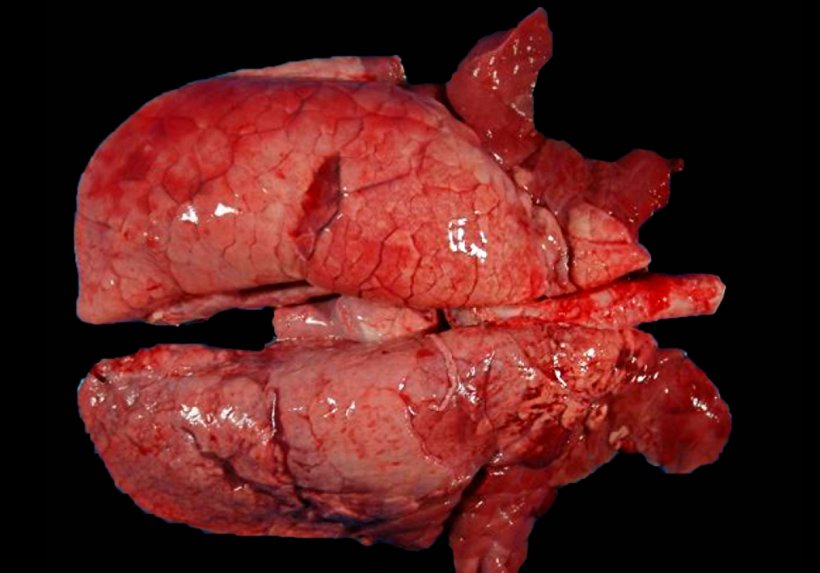

Chez les animaux co-infectés par M. hyopneumoniae et le SIV (figure 4), il a été observé que lorsque les porcs sont infectés par une souche faiblement virulente du virus de la grippe porcine après une infection par M. hyopneumoniae, il y a une augmentation significative des symptômes et lésions pulmonaires, démontrant que le mycoplasme est capable d'augmenter la virulence de ces souches de SIV.

Figure 4. Poumon d'un porc co-infecté par M. hyopneumoniae et le SIV. Zones de consolidation rouge dans les parties cranioventrales du poumon et quelques autres de moindre extension dans les lobes diaphragmatiques. Dans ces lésions cranioventrales, les lésions de M. hyopneumoniae et de SIV coexistent, ce qui ne permet pas de les distinguer macroscopiquement.